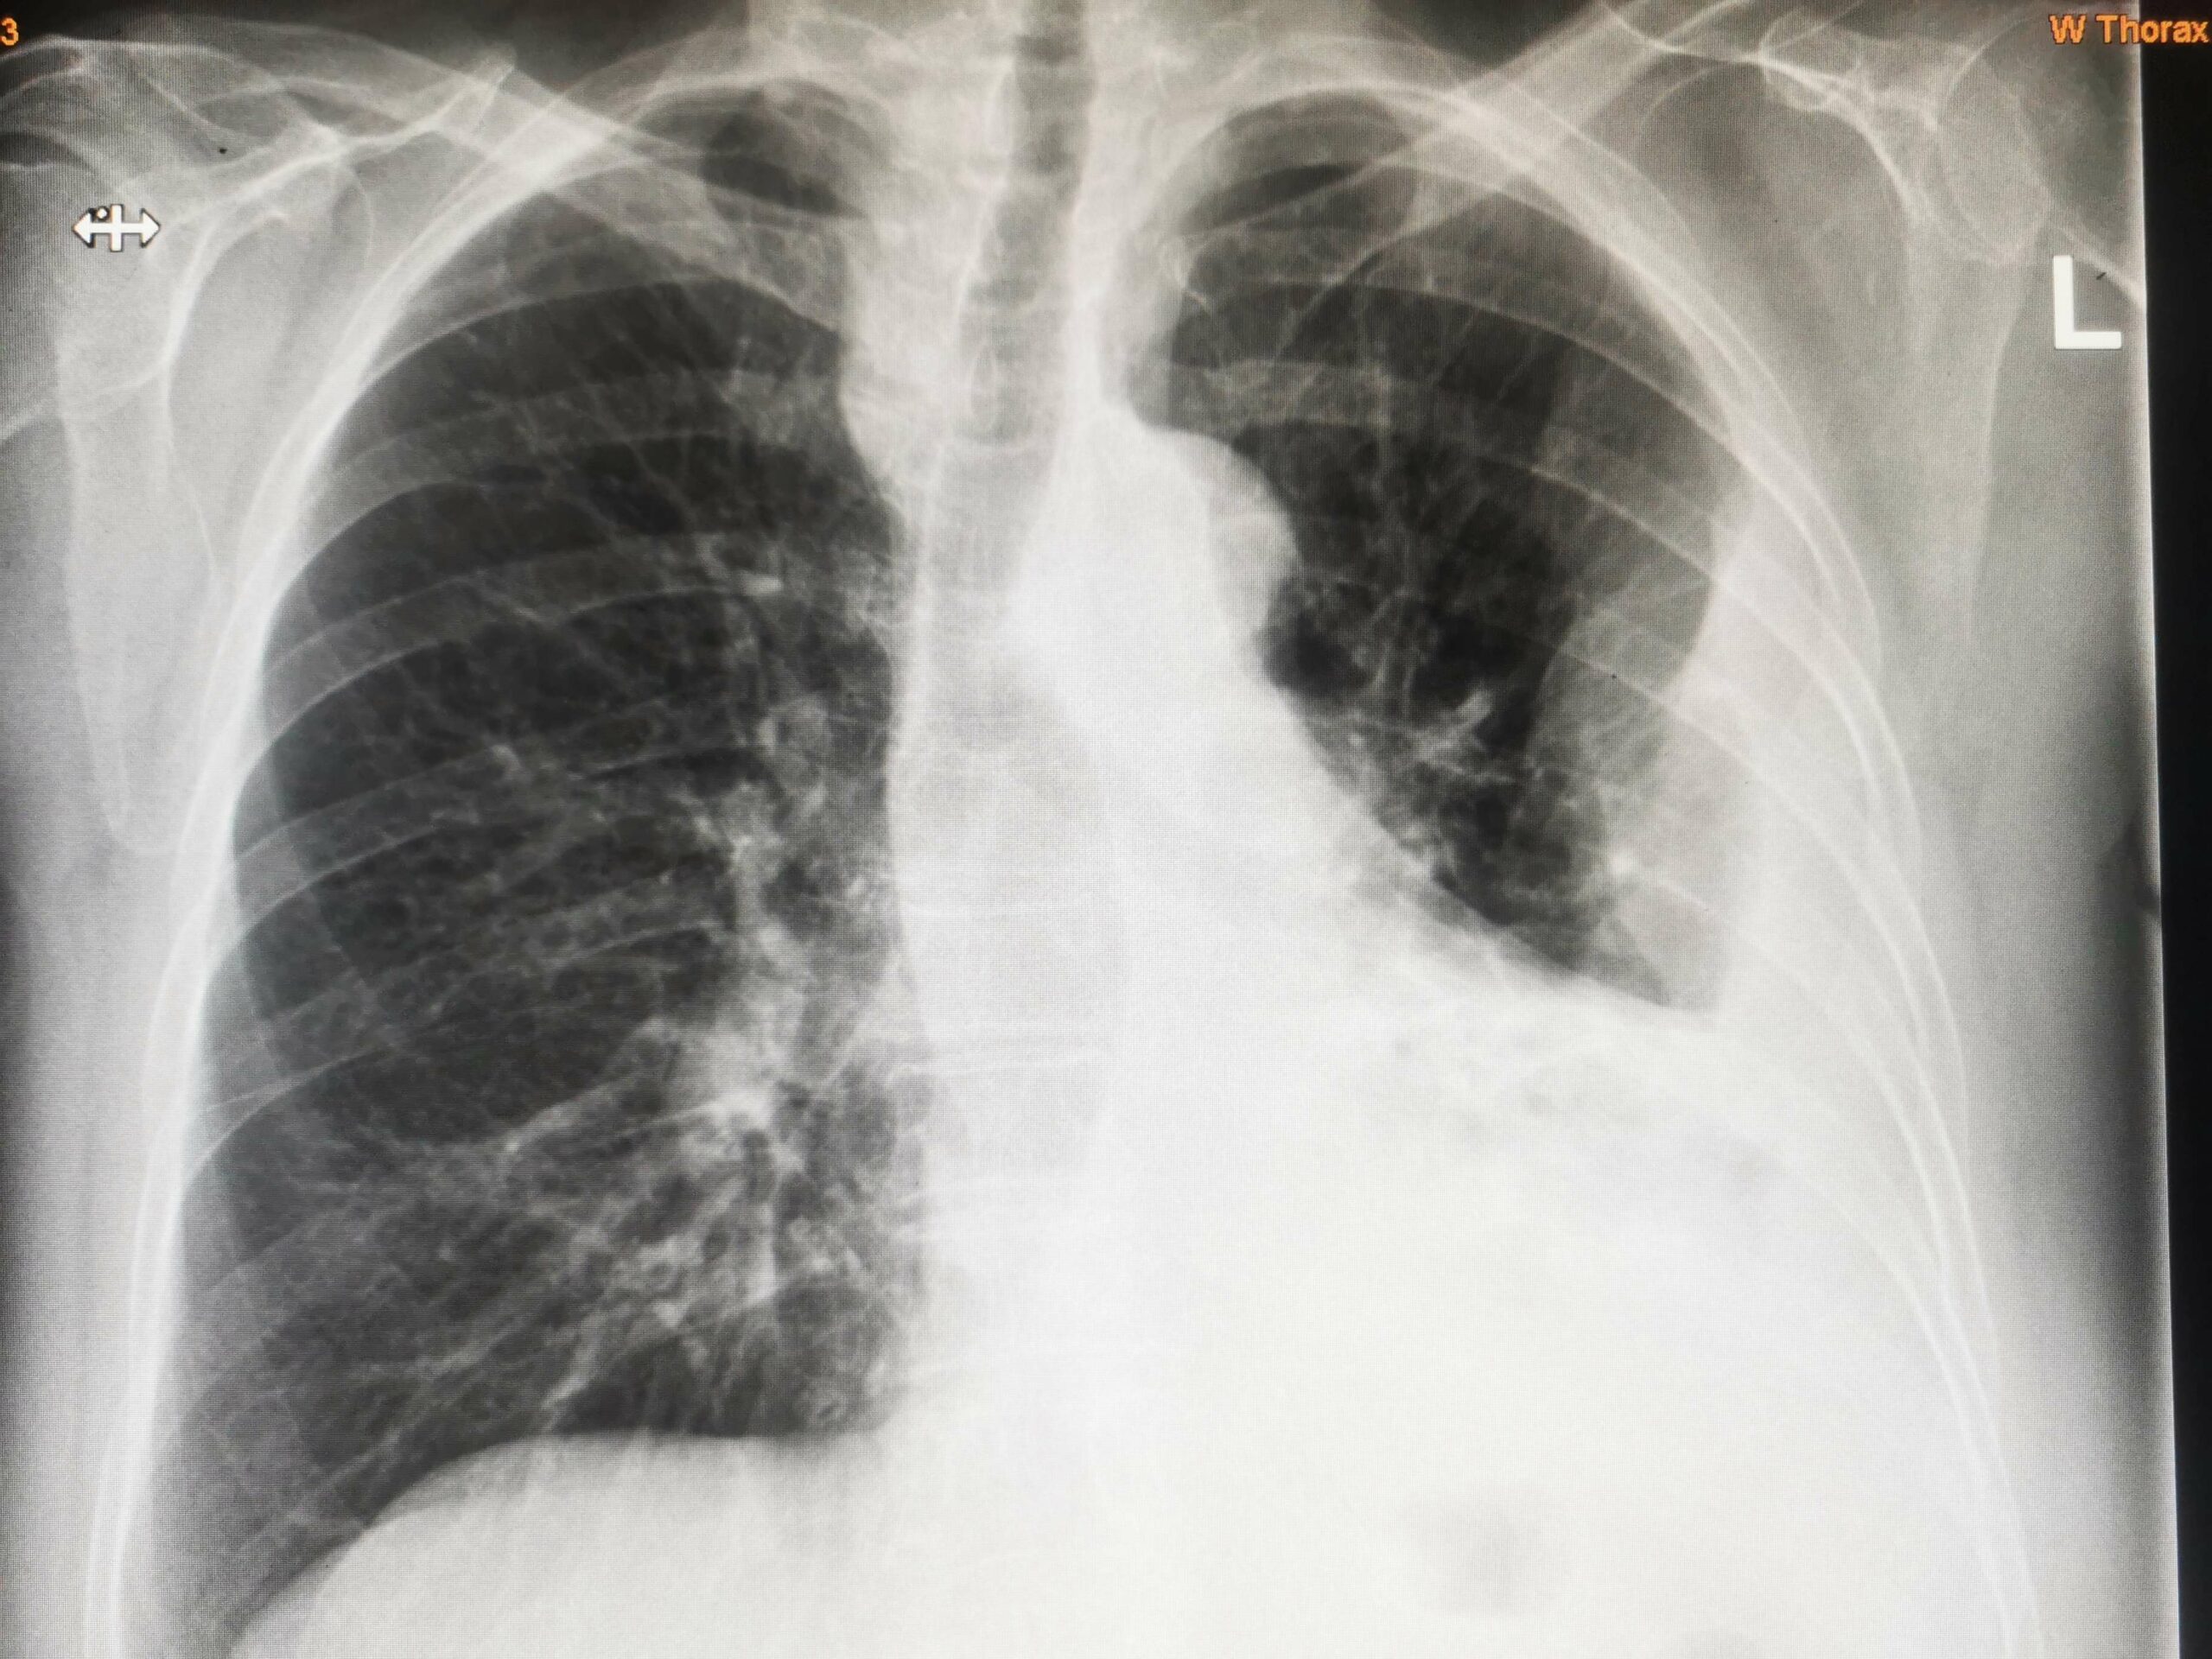

Röntgen teşhis kriterleri

Bir plevral efüzyon, akciğerleri ve göğüs duvarını çevreleyen doku katmanları arasındaki alan olan plevral boşlukta sıvı birikmesini ifade eder. Birçok tıbbi ortamda yaygın bir teşhis sorunudur. Göğüs radyografisi (X-ışını) genellikle bir plevral efüzyonu tanımlamak için kullanılan ilk basamak görüntüleme tekniğidir. Plevral efüzyonu teşhis etmek için kullanılan bazı radyografik işaretler ve kriterler şunlardır:

Kostofrenik Açının Küntleşmesi: Bu genellikle posteroanterior göğüs röntgeninde plevral efüzyonun en erken belirtisidir. Kostofrenik açı, genellikle keskin görünen, göğüs kafesi ile diyafram arasındaki açıdır. Plevral efüzyonla bu açı körelir veya belirsizleşir.

İçbükey Üst Arayüz veya Menisküs: Plevral sıvı, yerçekimi nedeniyle plevral boşluğun alt kısımlarında birikme eğilimindedir ve dik göğüs röntgenlerinde içbükey bir üst sınıra yol açar.

Mediastinal Kayma: Büyük plevral efüzyonlar mediastende (göğüs kafesinin merkezi kısmı) karşı tarafa kaymaya neden olabilir.

Opaklık: Büyük bir efüzyon durumunda, akciğerin tüm alt kısmı göğüs röntgeninde opak veya beyaz görünebilir, çünkü sıvı röntgenler radyografide beyaz görünür.

Göğüs röntgeni bir plevral efüzyonu teşhis edip efüzyonun boyutu ve yeri hakkında bilgi verebilirken, tipik olarak efüzyonun nedenini belirleyemeyeceğini unutmamak önemlidir. Etiyolojiyi belirlemek için torasentez (analiz için sıvının alınması) gibi daha ileri teşhis testleri gerekebilir.